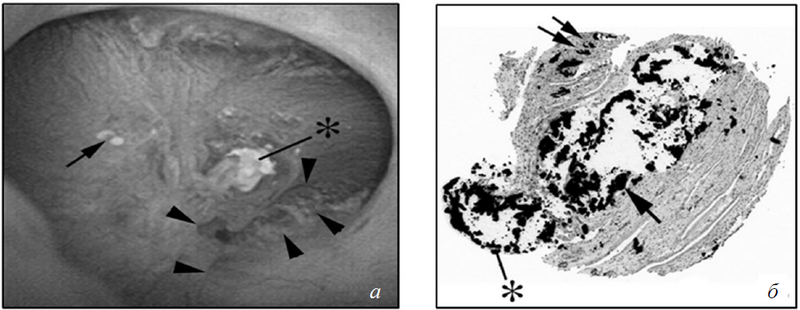

Не редко у пациентов с МКБ встречается закупорка протоков Беллини (ПБ), но роль этого явления в качестве источника конкрементов еще не доказана. Естественно предположить, что область этих «пробок», постоянно контактирующая с мочой с высоким насыщением CaOx и кальцием фосфата (СаР), будет в значительной степени способствовать нуклеации ГА и СаОх, становясь основой зарождающихся конкрементов [22], которые впоследствии отсоединятся и превратятся в клинически значимые камни, подлежащие удалению. Столь привлекательная формулировка, к сожалению, имеет довольно скудные доказательства. Хирурги видят заглушки Беллини как дилатированные и заполненные кристаллами протоки Беллини. Иногда кристаллы растут над заглушками в просвет чашечно-лоханочной системы (рис. 5 а, б).

Рис. 5. Вид заглушек Беллини у пациентов с брушитными конкрементами: а) эндоскопический вид почечного сосочка. Можно видеть впячивания (треугольники) на сосочке, чего не бывает у пациентов с CaOx-конкрементами. Как и у пациентов с CaOx-камнями, на почечных сосочках пациентов с брушитными конкрементами также могут визуализироваться бляшки Рэндалла (стрелка), хоть и в меньшем количестве. На сосочках заметны отложения кристаллов желтоватого цвета в области отверстий протоков Беллини (звездочка). Эти протоки, как правило, расширены и иногда наполнены кристаллами, которые выступают за пределы протоков и могут рассматриваться как основа для прикрепления конкрементов; б) биоптат кристаллических отложений в почечных сосочках (окраска по методу Ясуэ). Стрелками отмечены отложения кристаллов в просвете собирательных канальцев мозгового вещества рядом с петлей Генле. Кристаллические отложения значительно расширяют просвет этих канальцев и индуцируют повреждения клеток вплоть до обширного некроза. Вокруг мест интралюминальных отложений определяются воспаление и интерстициальных фиброз

У пациентов с ГА- и БР-конкрементами наблюдаются округлые разрастания на местах закупоривания — обычно около 1–2 мм (рис. 6, а–д). Такие разрастания в дальнейшем могут отрываться и увеличиваться в почечных чашках до 3 мм и более. С помощью высокоразрешающих микро-КТ-изображений (см. рис. 6) было доказано, что у ГА-пациентов эти «пробки» и разрастания состоят из ГА (см. рис. 6, а, б), в то время как у БР-пациентов базис конкрементов может содержать СаОх, БР и ГА с тонким поверхностным слоем CaOx (см. рис. 6, в, г). Поэтому вполне закономерно было бы предположить, что ГА- и БР-конкременты появляются на «заглушках», однако доказательств этому на сегодняшний день нет.

Рис. 6. Снимки заглушек Беллини: а, в, д, ж) световая микроскопия с участками разрастаний у пациентов с апатитными, брушитными конкрементами, после илеостомии и с первичным гиперпаратиреозом соответственно; б, г, е, з) микро-КТ в 3D-формате представленных камней. Пунктирная линия разграничивает заглушки и разрастания. Состав заглушек у пациентов с апатитными (а, б) конкрементами и с первичным гиперпаратиреозом (ж, з) целиком состоит из апатита. Заглушки у пациентов с брушитными камнями (в, г) представляют собой смесь брушита, апатита и CaOx, в то время как у пациентов с илеостомией (д, е) — из апатита и уратов. Разрастания у пациентов с апатитным камнеобразованием и пациентов с первичным гипертиреозом состоят преимущественно из концентрических слоев апатита, полностью из CaOx — у пациентов с илеостомами и смесью CaOx и брушита — у пациентов с брушитным камнеобразованием